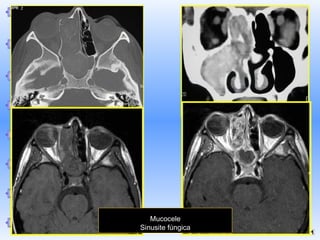

Mucocele

Sinusite fúngica